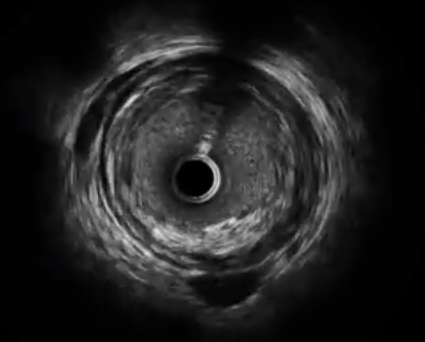

IVUSでは、このような映像で血管の断面を観察できます↓

このような映像で血管の断面を観察できるぞ!↓